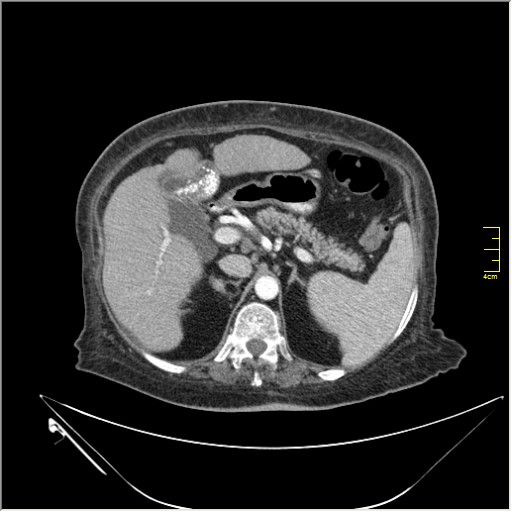

Весьма актуальная тема. Часто при проведении КТ исследования по тому или иному поводу, мы находим патологию, никак не связанную с клиникой пациента и не являющимся причиной обращения в кабинет КТ. Очень важно знать; как с этим быть, какие рекоммендации и действия необходимо предпринять. Для примера приведу одно наблюдение.

N.B. Все "находки" никак не были связаны с клиникой.

образование в правом надпочечнике

Incedentaloma правого надпочечника

Находки 2:

1.Образование правого надпочечника с плотностью жира, липома. Ничего делать не надо. По другим вариантам incidentalomas, Др. Капустин всё расписал.

2. Множество мелких конкрементов жёлчного пузыря, заполняющие до 50% просвета. С этим надо что-то делать. )))